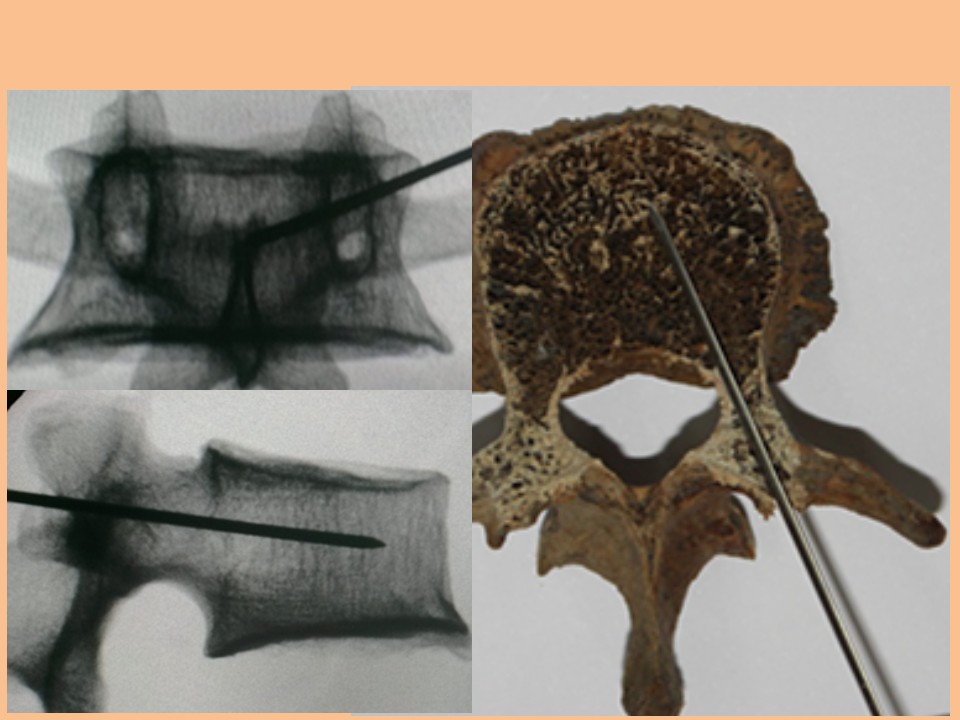

单侧穿刺的胸10椎体成形术

单侧穿刺椎体成形术的解剖学与影像学研究